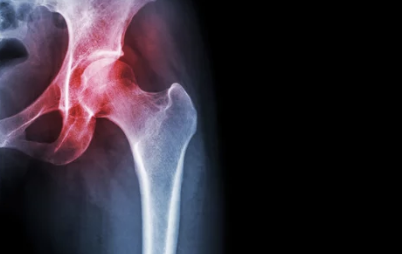

1️⃣ 퇴행성 고관절염

- 설명: 고관절 연골이 닳아 없어지면서 염증과 통증 발생

- 주로 나타나는 연령: 50세 이상 중장년층

2️⃣ 대퇴골두 무혈성 괴사

- 설명: 대퇴골의 머리 부분에 혈류가 차단되어 뼈가 괴사하는 질환

- 원인: 과음, 스테로이드 남용, 외상 등